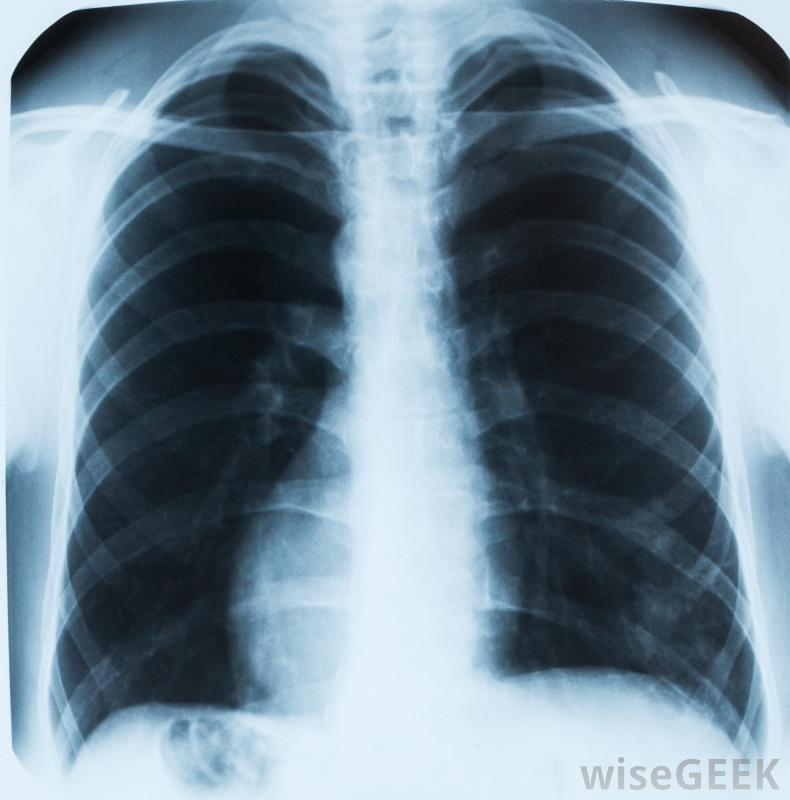

肺結核是一種潛在的嚴重的肺部疾病,由一種傳染性細菌引起。這種疾病在世界上許多地方很普遍,特別是在人口過多、衛生條件差、幾乎得不到優質保健的地方。一旦一個人被感染,他或她可能幾個月內都不會出現癥狀甚至數年。當疾病的跡象出現時,可能包括慢性濕咳、發燒,早期診斷和治療對于防止嚴重的肺損傷和肝或腦的并發癥是很重要的。肺部的X光片可以幫助醫生診斷肺結核幾種不同的結核分枝桿菌菌株都能引起感染。當被感染者咳嗽或打噴嚏時,這種細菌就會通過空氣傳播,很容易被其他人吸入。在肺部,細菌附著在內層,可以長時間休眠。事實上,大多數人根本不會出現癥狀,因為他們的免疫系統很強,足以抵御病原體。很小的兒童,老年人,免疫系統減弱的人患活動性肺結核的風險最高。肺結核的癥狀通常包括胸痛肺結核的第一個癥狀通常包括輕微的呼吸困難,偶爾咳嗽和喘息,以及胸痛。癥狀往往會在數周或數月內惡化,直到持續出現使人虛弱的問題。一個人可能開始咳血,發燒和發冷,而且一直感到疲勞。體重減輕,頸部淋巴結腫大,液體潴留也會發生。如果不治療,細菌可以從肺部和淋巴結擴散到其他重要器官,引起非常嚴重的疾病。醫生通常可以通過詢問癥狀和對胸部進行診斷性成像掃描來診斷肺結核電腦斷層掃描,肺部的斑塊通常表現為發炎、疤痕和變色。也可以在實驗室采集痰樣并進行分析,以確認診斷。有時,可能需要收集肺組織樣本以排除癌癥大多數活動性肺結核可以通過一個療程的抗生素治療治愈。醫生通常會開吡咯嗪酰胺,利福平,每天服用兩到三種其他藥物,至少持續六個月。患者在整個療程中繼續服用藥物是很重要的,即使他們的癥狀很快好轉,以確保細菌被完全根除。治療期間和治療后的頻繁體檢可以確認問題已得到解決利福平是肺結核患者的處方藥之一。